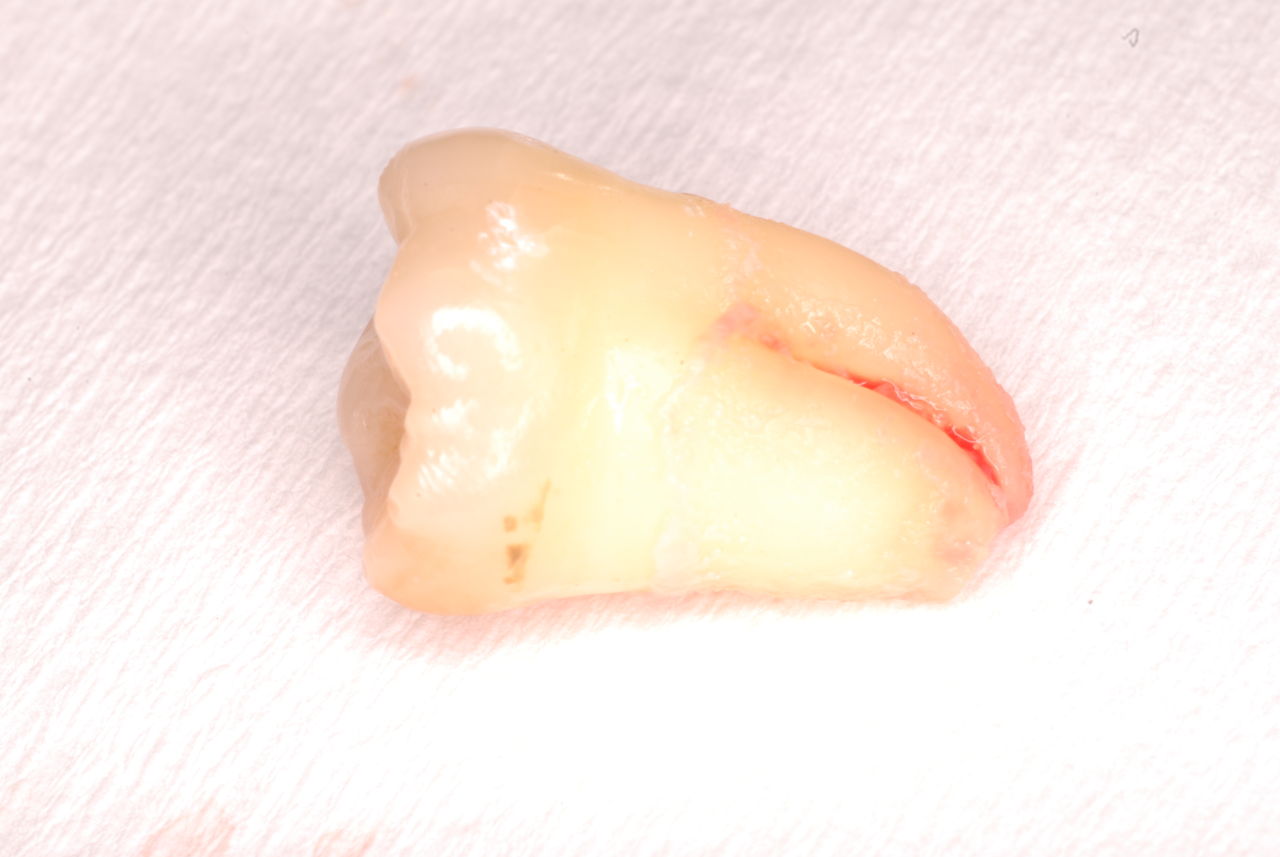

平成9年治療、虫歯と神経の処置、歯周病の治療

![a7fa4f9f-s[1]](https://livedoor.blogimg.jp/netdental/imgs/4/2/42470ffa.jpg)

2012,7月来院

欠けたところを埋めておしまいです。